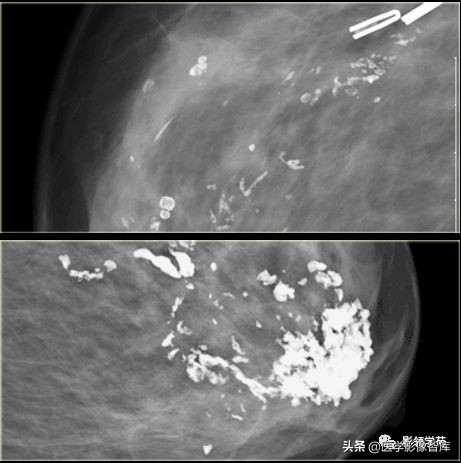

细小多形性钙化

阶段性或线性,大小和形状多变,<0.5mm, 25-40%为恶性。

BI-RADS5,手术证实为DCIS。

阶段性分布,分为BI-RADS5,手术证实为高级DCIS。

浸润性导管癌,多形性钙化、线虫状、分支杆状钙化。

女,50岁,多簇状细小多形性钙化,右乳外上浸润性导管癌。

不规则肿物伴多形性钙化,浸润性导管癌